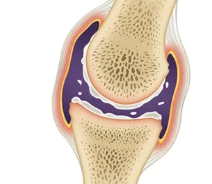

관절염은 뼈들이 만나는 지점인 관절에서 발생하는 질환으로, 이로 인해 관절 연골이 파괴되고 염증이 발생합니다. 이러한 관절은 인체의 움직임을 원활하게 하기 위해 상당히 중요한 구조로, 뼈들의 끝을 덮고 있는 연골은 마치 부드러운 쿠션처럼 작용합니다.

더불어, 관절을 둘러싼 활막이라 불리는 섬유질 막은 마찰을 최소화하고 관절 내부에서 움직임을 원활하게 합니다. 이 활막은 또한 활액을 생성하여 관절 내에서 뼈 사이의 마찰을 줄여주는 역할을 합니다.